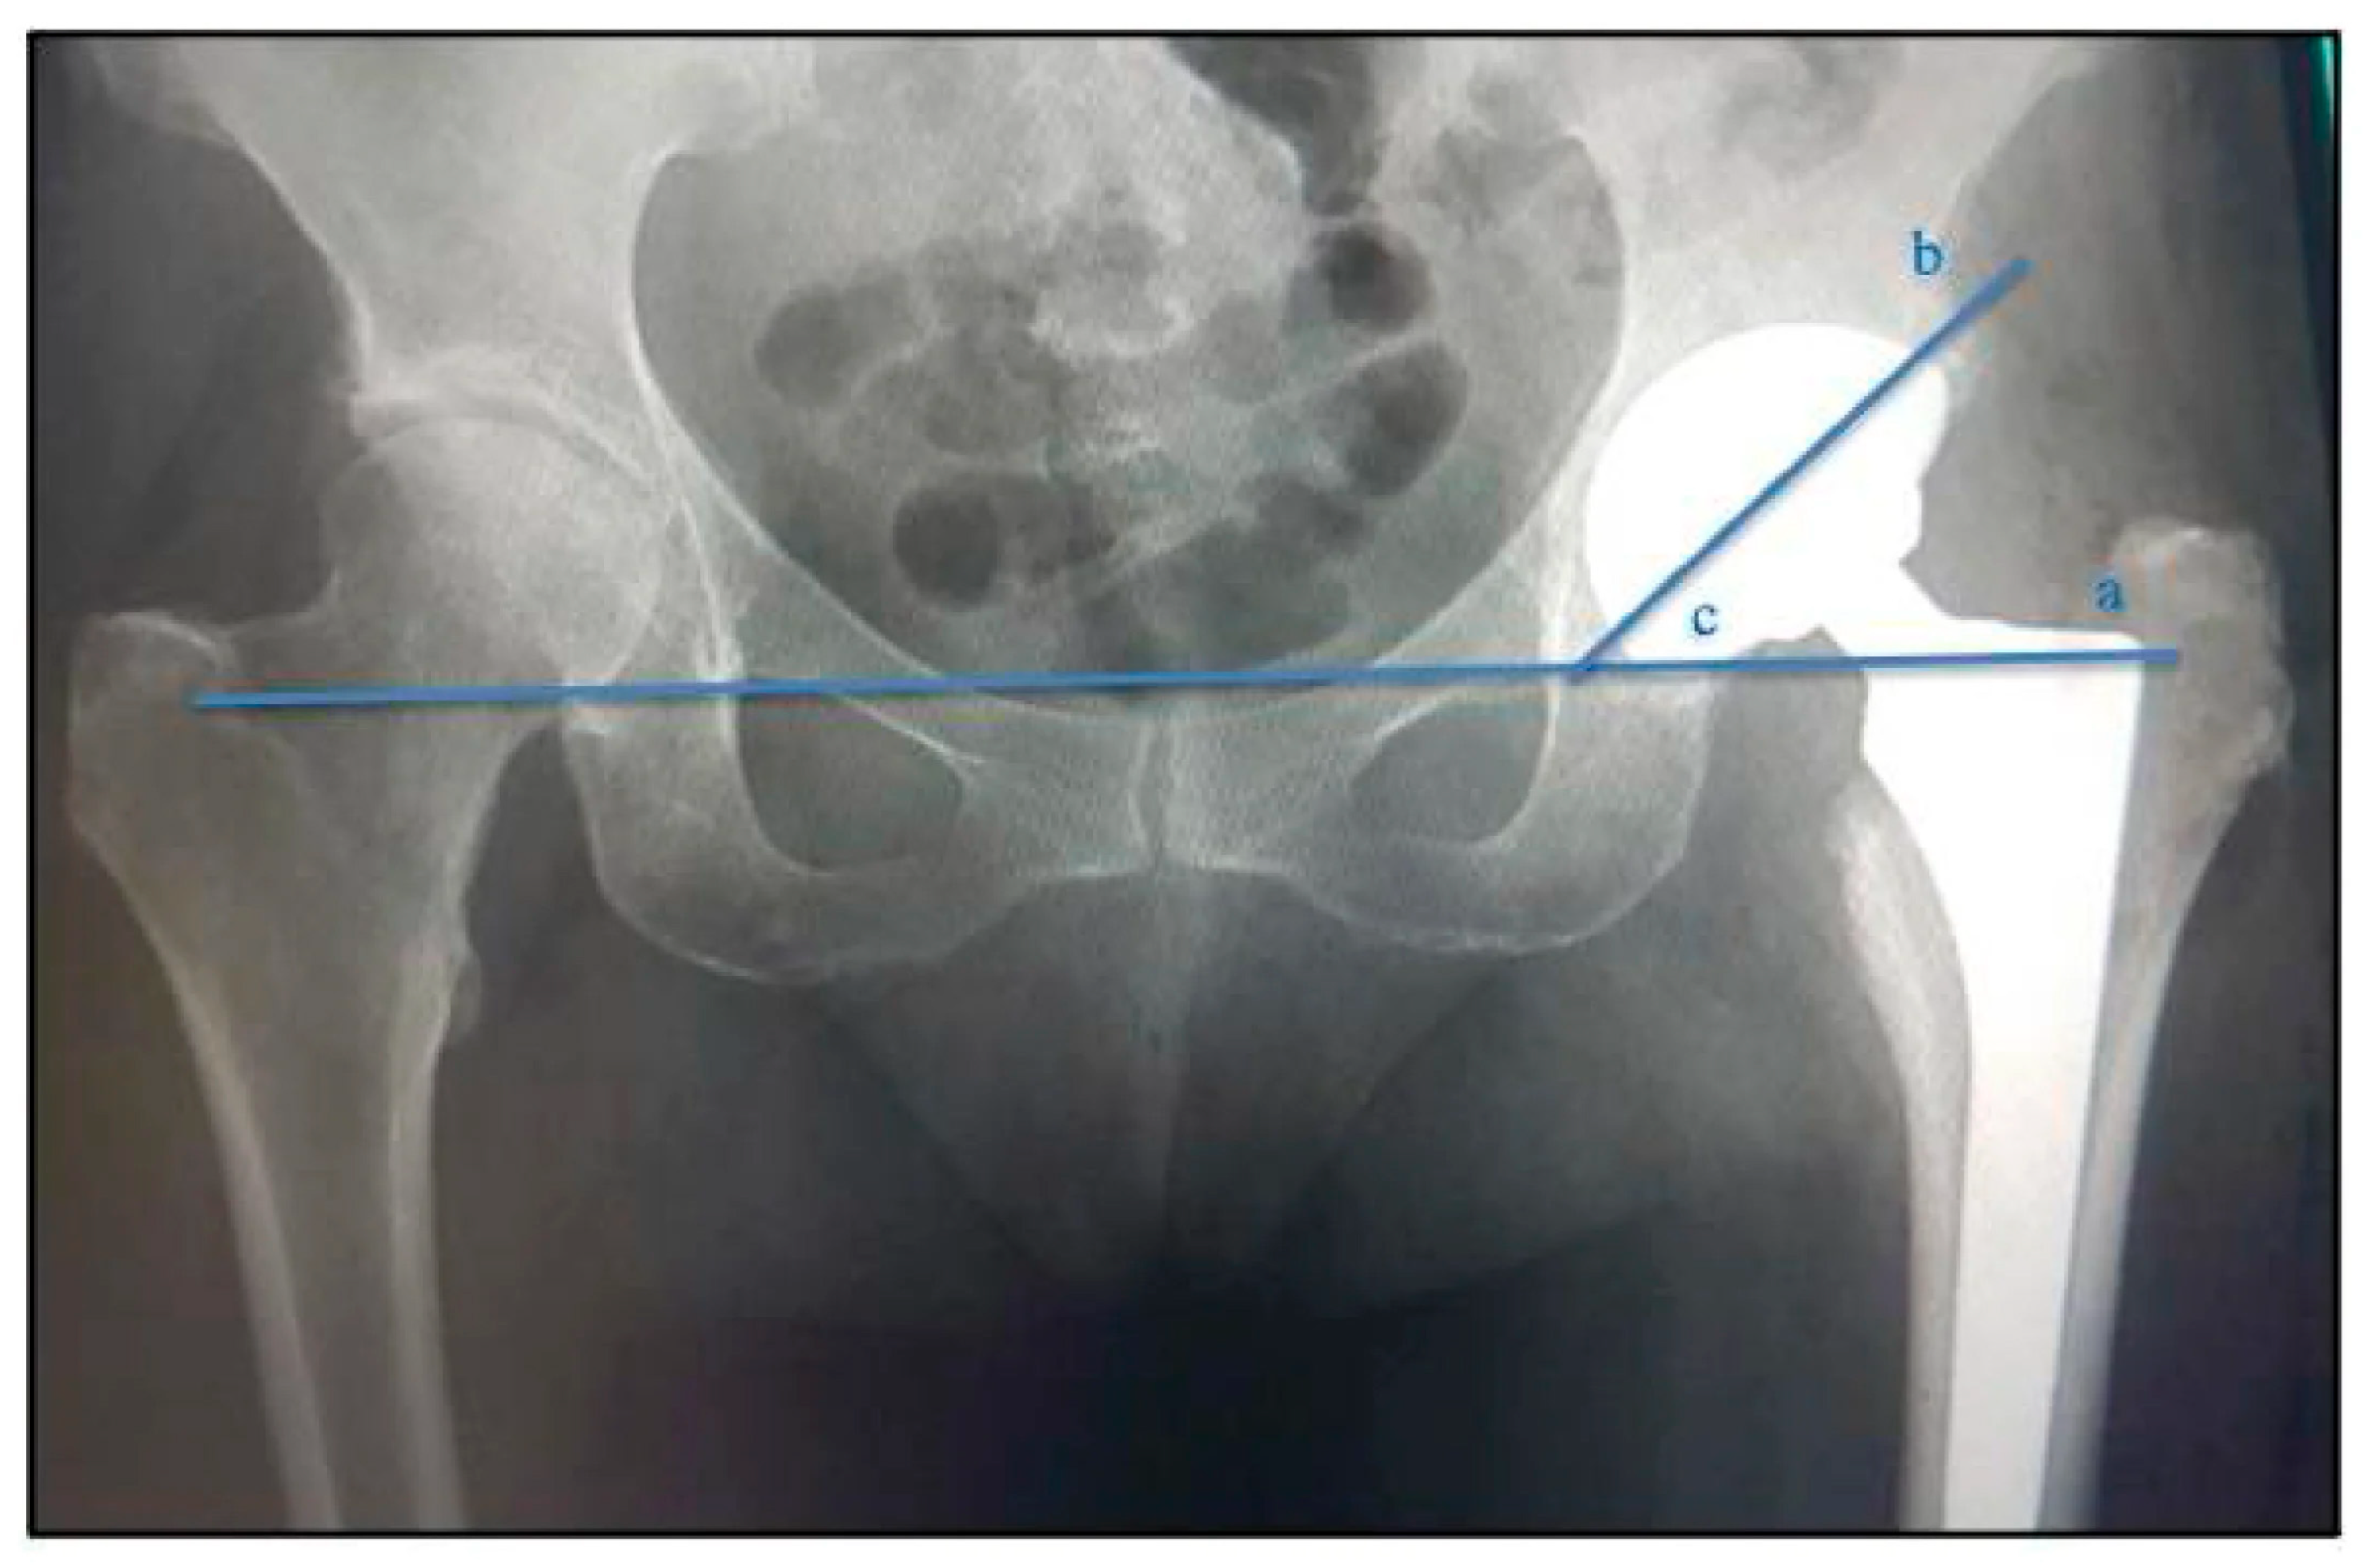

Acetabular component positioning angle measurement. (a)—line that touches the ischial tuberosities; (b)—line through the axis of the largest diameter formed by the projection of the metallic ring on the radiograph; (c)—acetabular angle. [14] © MDPI 2023.

Ceramic-on-ceramic (CoC) bearings are considered one of the most reliable long-term friction pairs in artificial joints due to their extremely low wear rate and excellent biocompatibility. However, recent clinical follow-ups and prosthesis retrieval analyses indicate that despite their superior overall wear control, CoC bearings still face a series of clinical issues closely related to their tribological behavior. As shown in Figure 1, These problems not only affect patients’ subjective experiences but also limit their application scope to some extent. This chapter systematically summarizes the typical tribological issues of ceramic-on-ceramic bearings and their potential causes, starting from clinical manifestations.

Figure 1.

Underwent THA using the MD® ceramic acetabular component devices (ceramic head with ceramic acetabular insert) associated with the MD6® Phenom® femoral rod type. [14] © MDPI 2023.